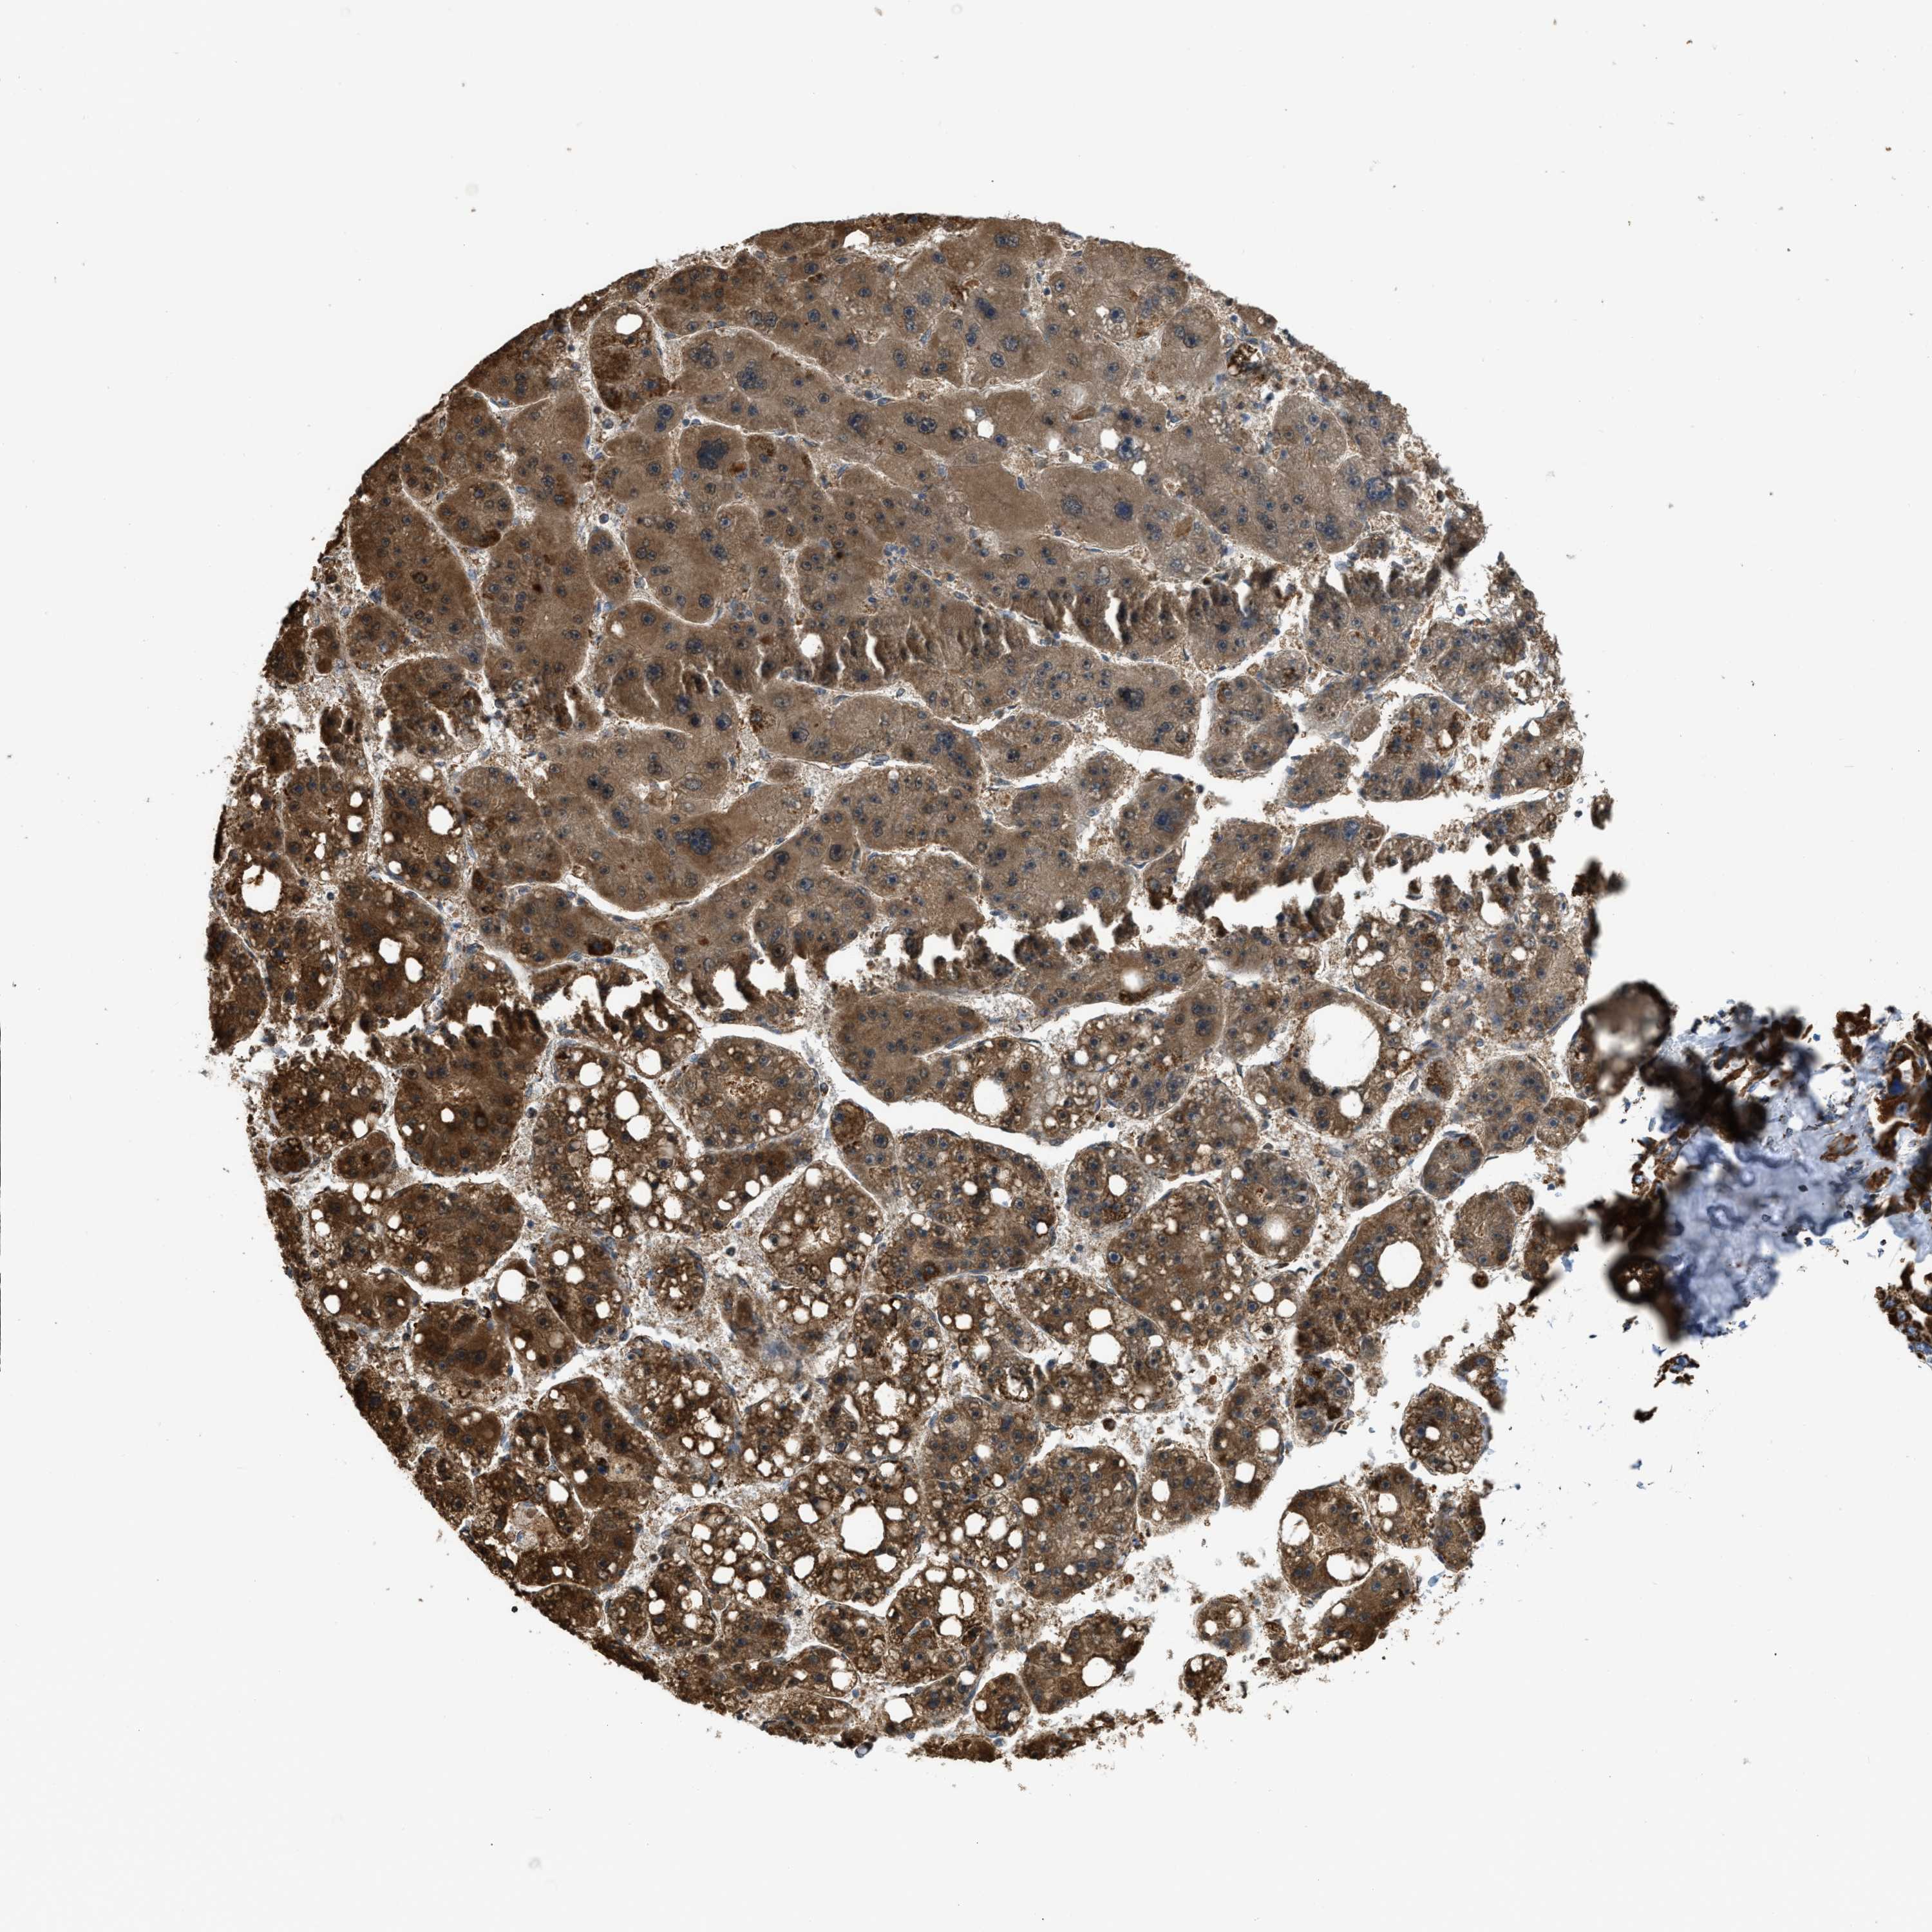

LIVER CANCER - Protein expressioni

A mouse-over function shows sample information and annotation data. Click on an image to view it in a full screen mode. Samples can be filtered based on level of antibody staining by selecting one or several of the following categories: high, medium, low and not detected. The assay and annotation is described here.

Note that samples used for immunohistochemistry by the Human Protein Atlas do not correspond to samples in the TCGA dataset.

Antibody stainingi

Antibody staining in the annotated cell types in the current human tissue is reported as not detected, low, medium, or high, based on conventional immunohistochemistry profiling in selected tissues. This score is based on the combination of the staining intensity and fraction of stained cells.

Each image is clickable and will lead to virtual microscopy that enables deeper exploration of all samples and also displays staining intensity scores, fraction scores and subcellular localization as well as patient and tissue information for each sample.

Antibody HPA018910

Antibody HPA018921

Antibody HPA018923

Staining

High

Medium

Low

Not detected

Intensity

Strong

Moderate

Weak

Negative

Quantity

>75%

75%-25%

<25%

None

Location

Nuclear

Cytoplasmic/membranous

Cytoplasmic/membranous,nuclear

Cholangiocarcinoma

Carcinoma, Hepatocellular, NOS